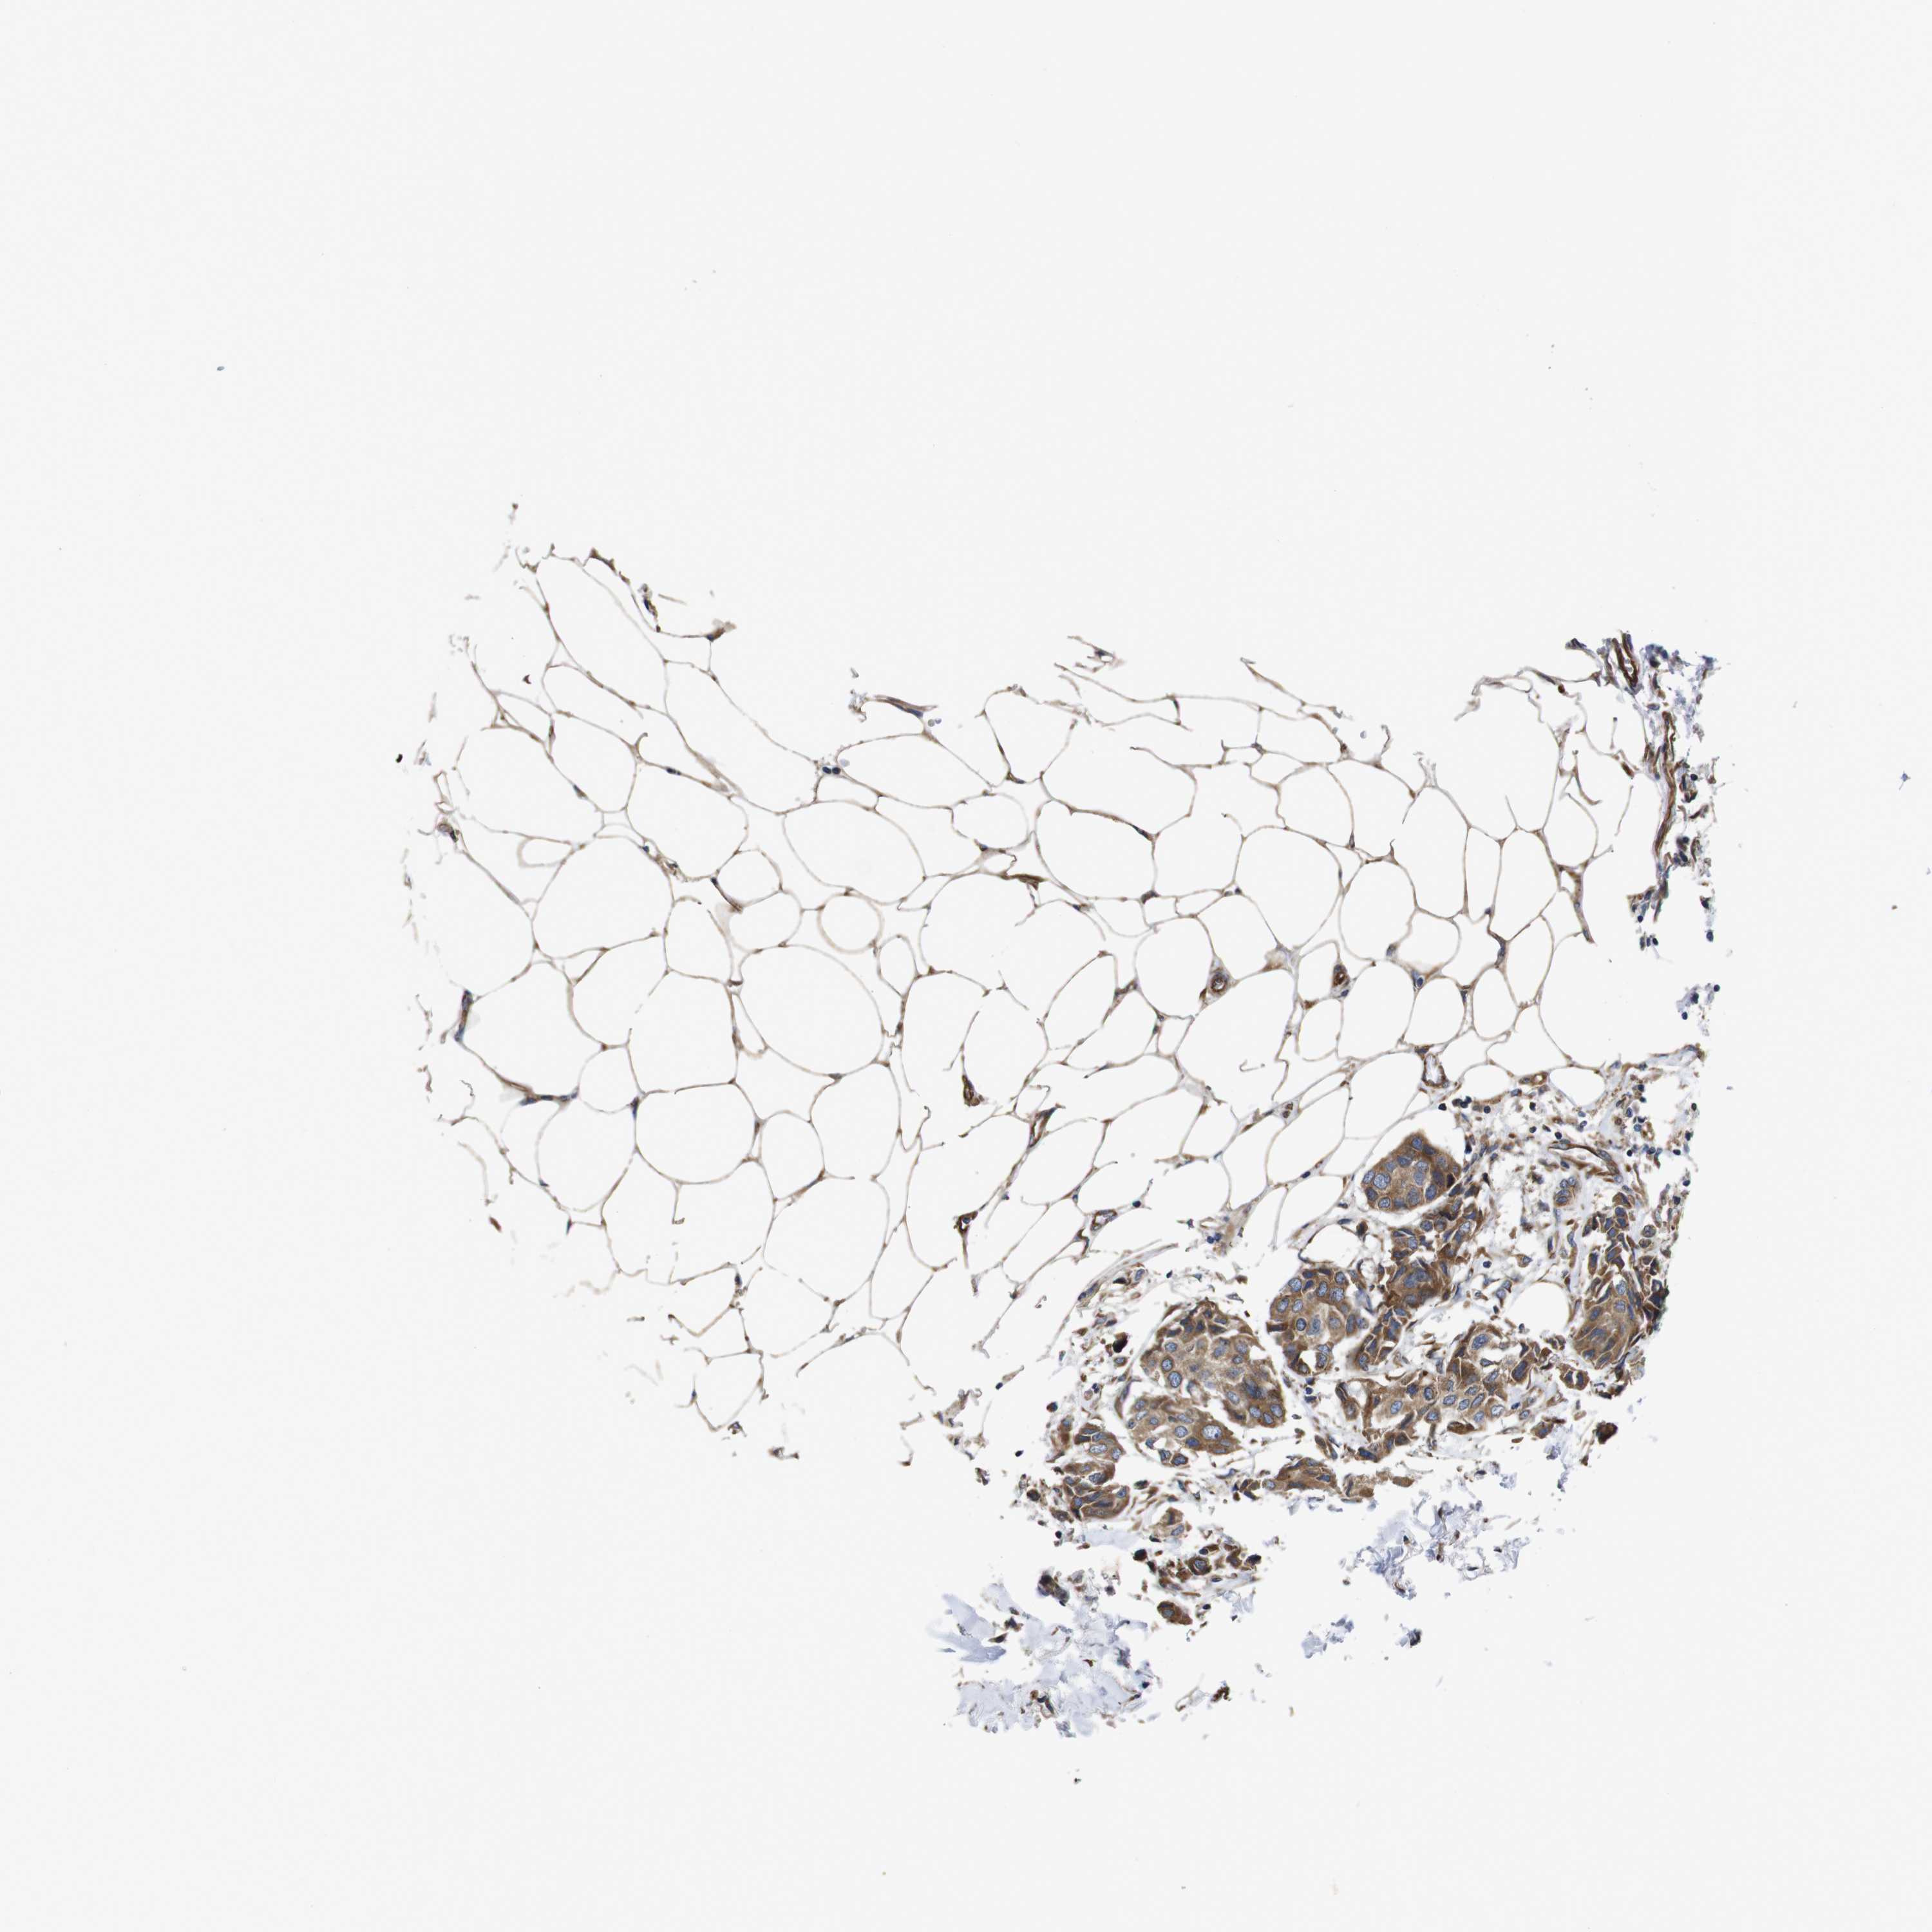

CANCER BREAST CANCER Show tissue menu

BRCA TCGA BRCA VALIDATION PROTEIN EXPRESSION